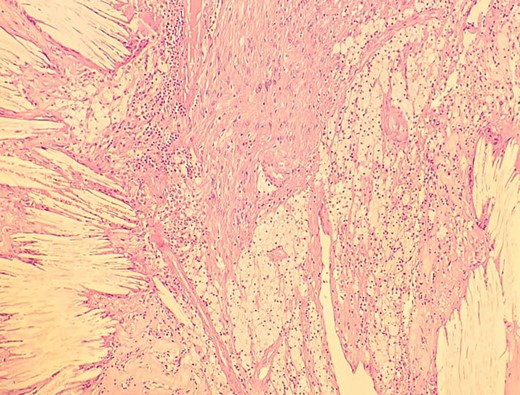

A man in his 30s presented with symptoms suggestive of irritable bowel symptoms with increased bowel movements coinciding with the onset of colicky abdominal pain for the past 8 months. The bowel movements relived his pain and had no remission from his symptoms. He had no relevant medical comorbidities in the past. The patient had normal vitals. There were no physical exam abnormalities except for a slight fullness in the left renal angle (Fig. 1). There was nothing significant on a rectal examination. An X-ray of the chest showed normal findings. Blood investigations showed: haemoglobin 130 g/l, total leukocyte: 7.4 × 109/l, serum creatinine 0.52 mg/dl, fasting blood sugar 90 g/dl, alanine transaminase 26 U/L, aspartate transaminase 42 U/L, alkaline phosphatase 32 U/L and total bilirubin 0.8 mg/dL. Ultrasonography showed a 10-cm mass, with mixed echogenicity. Posterior to the left kidney. Colonoscopy was normal. An abdominal CT scan showed a paravertebral tumour with peripheral enhancement and heterogenous contrast within the tumour (Fig. 2). The tumour showed high intensity on a T2-weighted MRI (Fig. 3). The left kidney and colon were displaced anteriorly. Fine-needle aspiration biopsy was inconclusive. The clinical diagnosis was a retroperitoneal schwannoma. On laparotomy, the left colic vessels appeared to be splayed by the tumour (Fig. 4). The tumour 11 × 6 × 3 cm3 (Fig. 5), which seems to be arising from the L2 nerve, was resected completely (Fig. 6). The patient had no sensory or motor loss postoperatively. He was discharged without complications on the 10th postoperative day. His colonic symptoms had disappeared after surgery. The gross appearance of the resected tumour showed cysts and haemorrhage patches (Fig. 7). Histopathology showed areas of hypercellularity (Antony A) and hypocellularity (Antony B) with degenerative changes leading to nuclear atypia and cystic spaces, typical of an ancient schwannoma (Figs 8–11). Immunohistochemistry with S-100 was positive (Fig. 12). He was devoid of digestive symptoms or radiological evidence of recurrence at 12 months.

Low-resolution 200x H&E histopathology image of the tumour showing hypercellular (Antony A) areas.